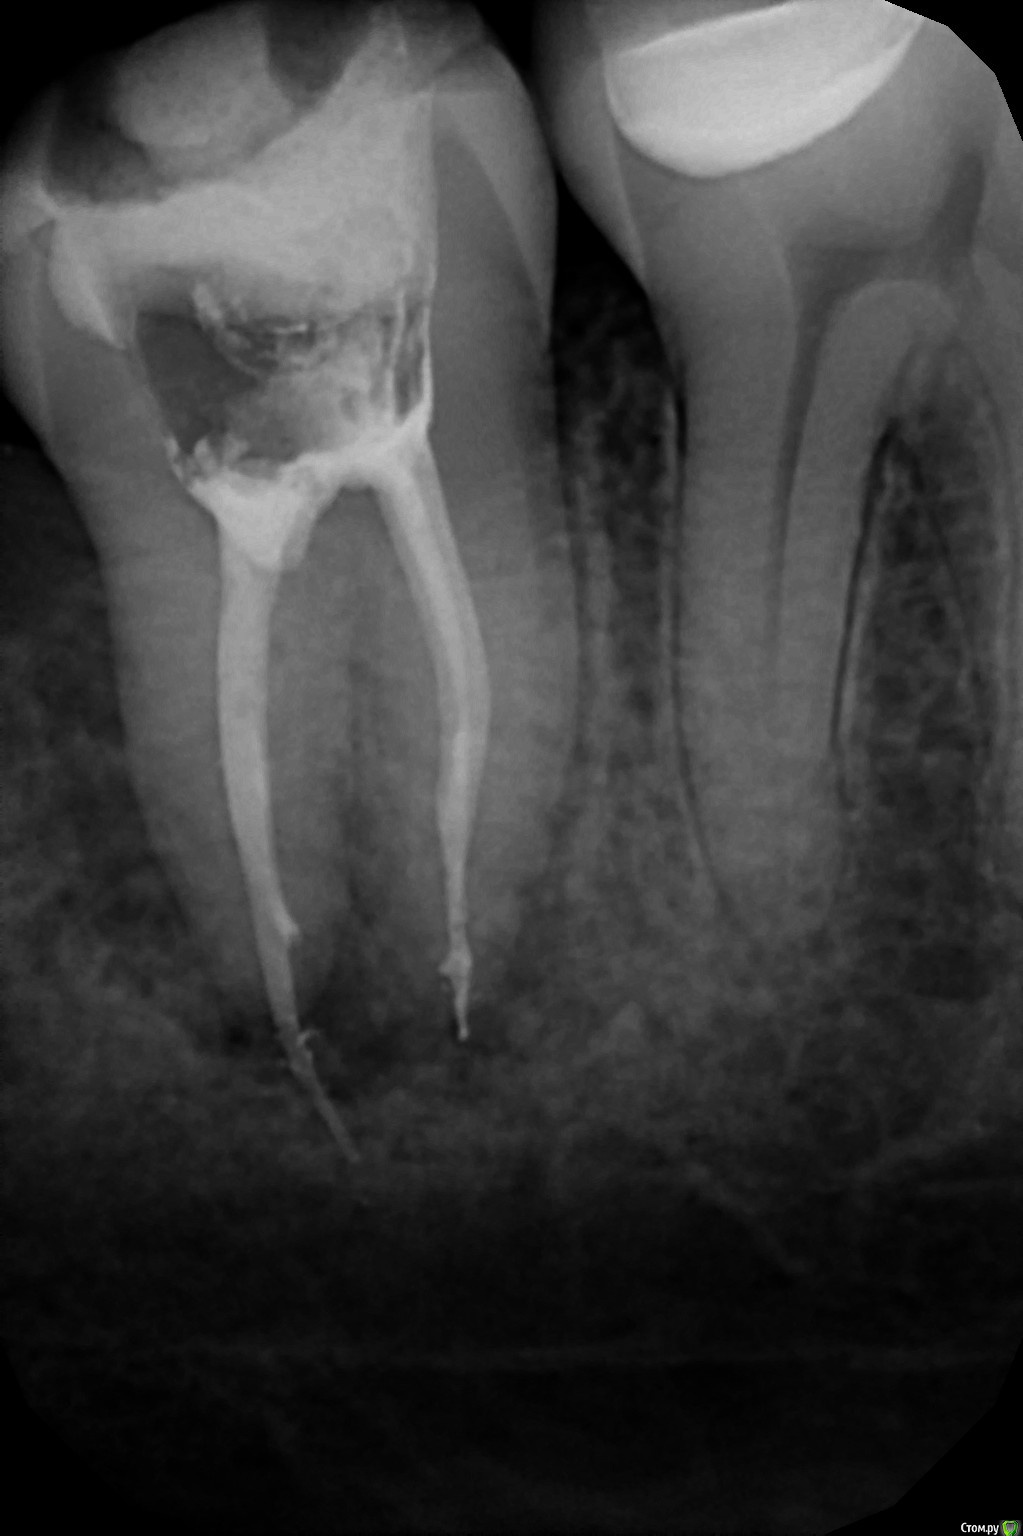

lunatik--26 Опубликовано 3 мая, 2017 Автор Поделиться Опубликовано 3 мая, 2017 (изменено) Полечила зуб. Диагноз поставили периодонтит. Прочистили каналы (2 шт.), положили лекарство и 2 недели с временной пломбой сказали ходить. Потом промыли и запломбировали каналы и опять поставили временную пломбу. Я сделала снимок и на нем видно, что часть пломбировочного материала вышла за пределы зуба. Но боли нет, каналы пломбировали дней 5 назад. Как считаете, надо ли переделывать пломбировку канала? Изменено 3 мая, 2017 пользователем lunatik--26 Ссылка на комментарий

St. Опубликовано 3 мая, 2017 Поделиться Опубликовано 3 мая, 2017 По последнему снимку точно периодонтит))Из описания все сделано верно. Да, есть избыточный материал за пределами корня, однако острой необходимости что-либо переделывать я не вижу. Тем более если ничего не болит. Понаблюдайте за зубом. Через 6 и 12 мес нужно будет сделать контрольные снимки Ссылка на комментарий